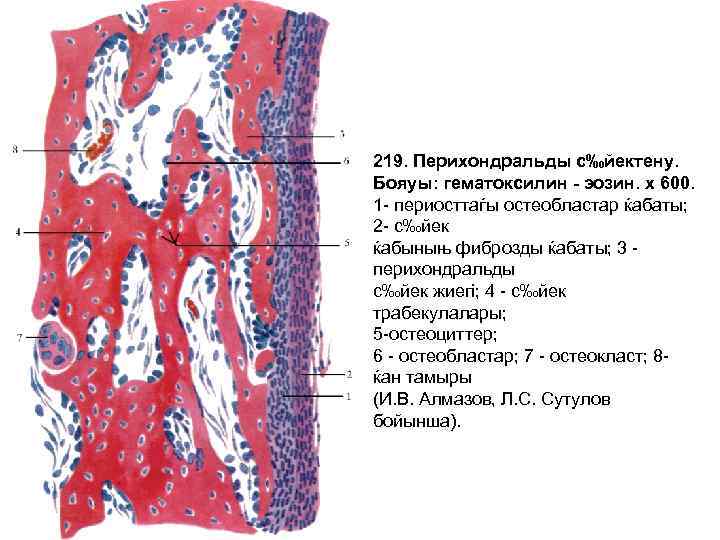

219. Перихондральды с‰йектену. Бояуы: гематоксилин - эозин. х 600. 1 - периосттаѓы остеобластар ќабаты; 2 - с‰йек ќабыныњ фиброзды ќабаты; 3 перихондральды с‰йек жиегi; 4 - с‰йек трабекулалары; 5 -остеоциттер; 6 - остеобластар; 7 - остеокласт; 8ќан тамыры (И. В. Алмазов, Л. С. Сутулов бойынша).